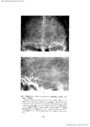

第3脳室近傍腫瘍の神経放射線診断-脳血管撮影を中心に- III 主に第3脳室の側方に発育する腫瘍(2)